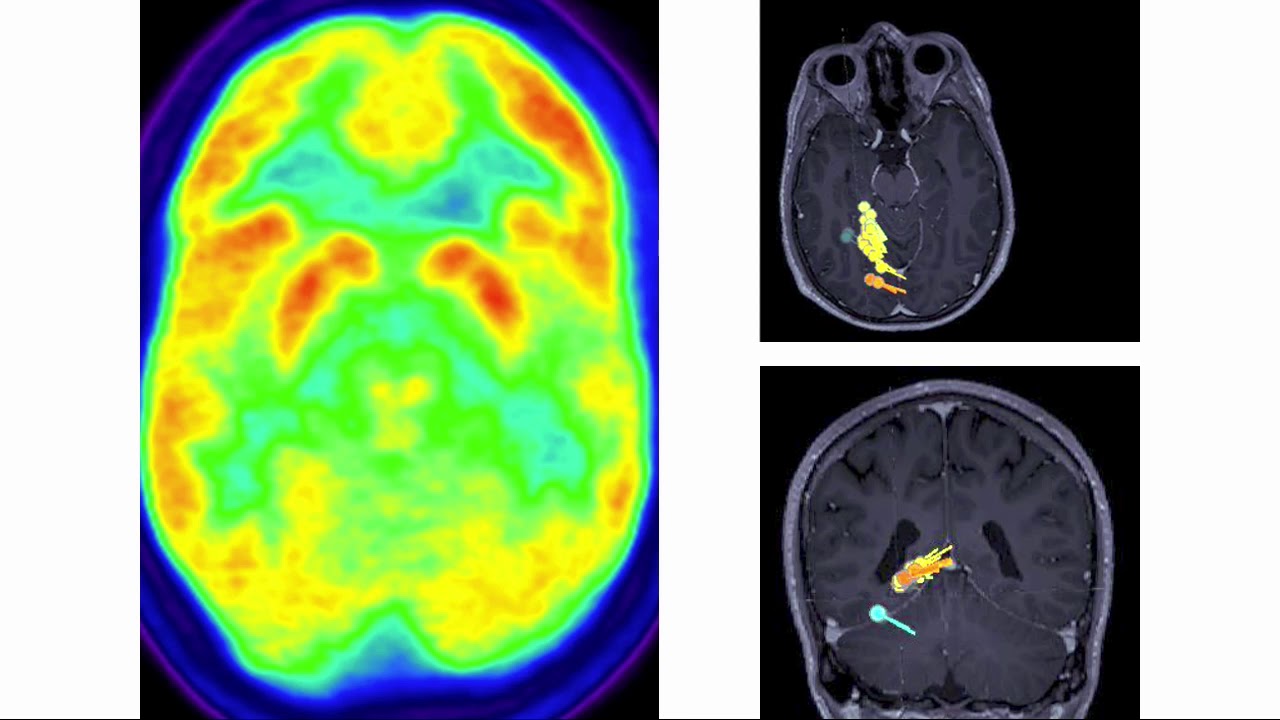

Neurólogo especializado en Epilepsia en todas las edades, tanto en edad pediátrica como en adultos. Director del Departamento de Neurociencias Clínicas del Hospital Blua Sanitas Valdebebas, Madrid, y de la Unidad de Epilepsia de este grupo, un equipo multidisciplinar único en sus características en España. Consulta y unidad de diagnóstico y tratamiento de epilepsia compleja en Madrid. También posibilidad de vídeoconsulta online. Especialista en crisis funcionales, las antiguamente conocidas como pseudocrisis, crisis psicógenas no epilépticas o conversivas, con el primer equipo multidisciplinar para su cuidado en España. Consulta y genética privada con ingresos, urgencias y pruebas de la máxima calidad cubiertas por seguros (vídeo-EEG prolongado, resonancia cerebral 3T). Visión multidisciplinar, estimulación, neurodesarrollo, neuropsicología, neuronutrición y conducta. Cirugía de epilepsia con técnicas mínimamente invasivas. Nuevos ensayos clínicos con terapias de precisión. Unidad de crisis funcionales (psicógenas no epilépticas o disociativas), la única multidisciplinar en España. Segundas opiniones, seguimiento estrecho multidisciplinar y evaluación de pruebas complementarias: neuroimagen (resonancia magnética de alta definición, PET, magneto-EG, resonancia funcional), estudios neurofisiológicos (vídeo-electroencefalografía prolongada) o genéticos (panel de genes, array-CGH, exoma, genoma), metabólicos e inmunológicos (neuroinmunología en LCR y sangre), así como de valoraciones cognitivas y de neurodesarrollo para evitar efectos adversos de fármacos y de impacto en la calidad de vida más allá de las crisis epilépticas.